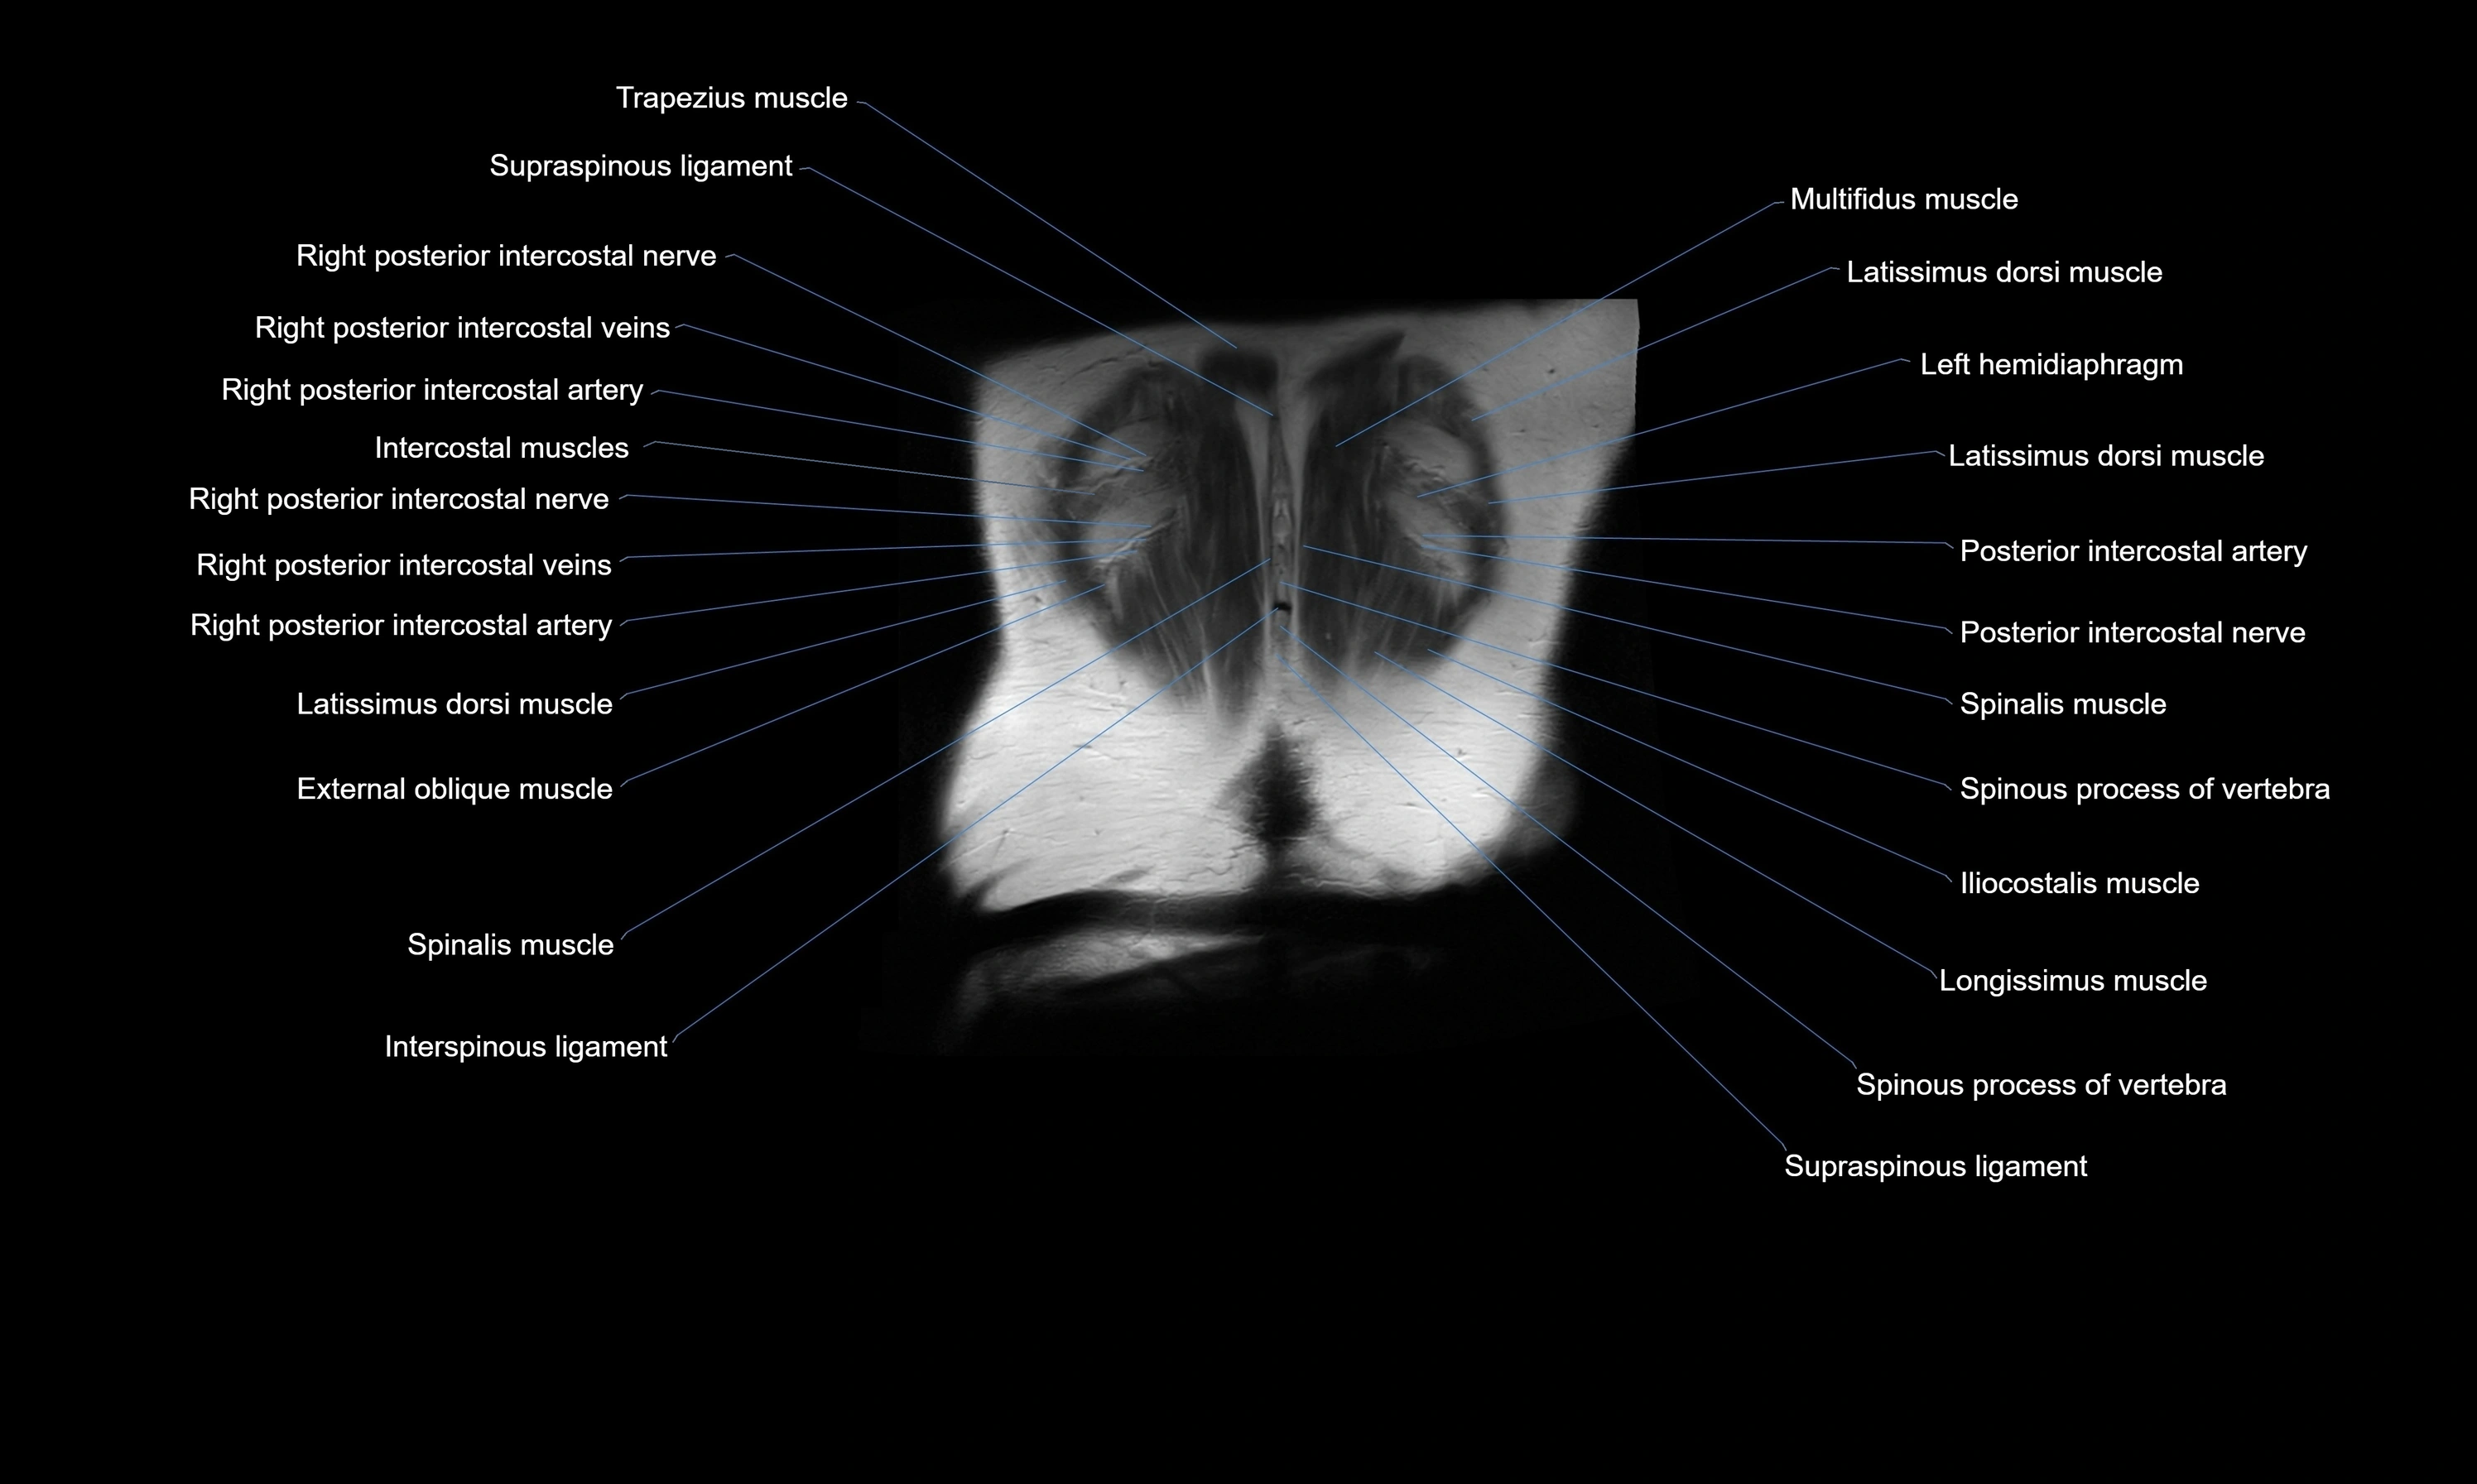

MRI images